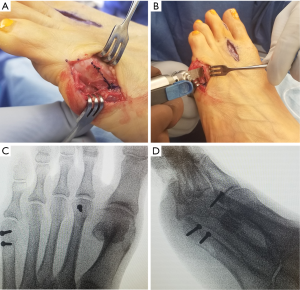

Another reported technique for management of type I bunionette deformities is the subcapital oblique osteotomy (Figure 5). Cooper and Coughlin demonstrated, in a retrospective review of 16 feet with a follow up of approximately 3 years, reliable clinical results for correction of type I deformities (16). They reported improvement in patient satisfaction, pain control; however, there was no significant improvement in IMA 4–5 angle at post-operative evaluation. We have found this procedure to have more flexibility than the chevron osteotomy. In addition to translating the metatarsal head laterally, by angling the saw blade slightly, the metatarsal head may be elevated to alleviate plantar pressure as well.

When addressing increased IMA 4–5 angles or increased lateral bowing, diaphyseal osteotomies are preferred. Adapted from hallux valgus surgery, Coughlin described an oblique osteotomy of the metatarsal shaft (similar to the Ludloff osteotomy described for hallux valgus), in conjunction with lateral condylectomy and distal MTP realignment to correct bunionette deformities (Figure 6). In his study, Coughlin reported 93% of good or excellent outcomes in 30 feet treated in this manner (8). Recently, Waizy et al. demonstrated improvement in patient satisfaction, radiographic measurements of IMA 4–5 angle and lateral bowing with a reverse Ludloff osteotomy for type II and type III bunionette deformities. They reported no complications or revisions from their procedure (24). Shi et al. documented several studies who reported similar outcomes with Ludloff variants and scarf osteotomies for type II and type III bunionette deformities (2).